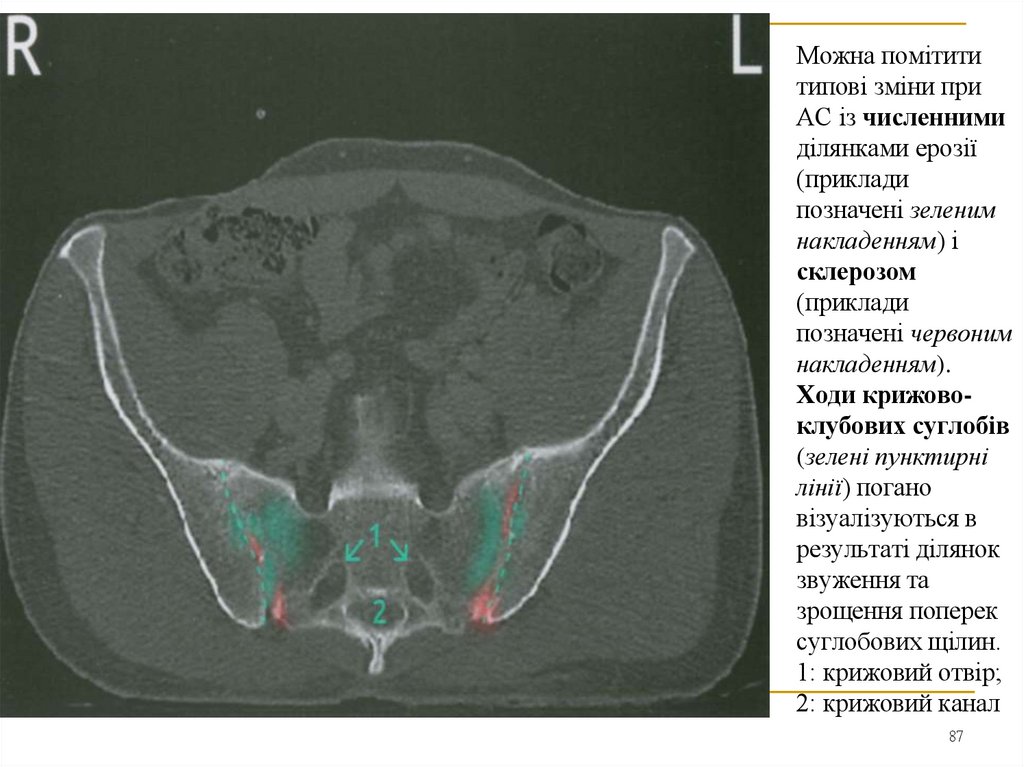

Можна помітити

типові зміни при

АС із численними

ділянками ерозії

(приклади

позначені зеленим

накладенням) і

склерозом

позначені червоним

накладенням).

Ходи крижовоклубових суглобів

(зелені пунктирні

лінії) погано

візуалізуються в

результаті ділянок

звуження та

зрощення поперек

суглобових щілин.

1: крижовий отвір;

2: крижовий канал

87